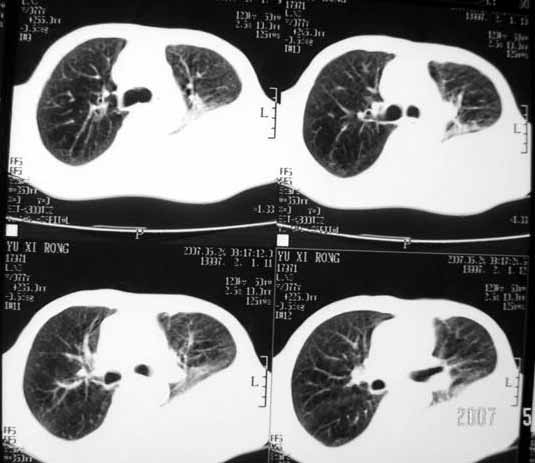

以下是引用luochengyi在2007-5-24 14:33:00的发言:[br]考虑左下肺癌。左侧胸腔积液。

以下是引用adams在2007-5-24 17:12:00的发言:[br]支持“考虑左下肺癌,左侧胸腔积液,建议胸水检查”。[br] [br]

以下是引用fumaogui在2007-5-24 16:20:00的发言:[br]左侧胸腔积液.[br]左下叶不张考虑中心型肺癌[br]建议纤支镜检查.